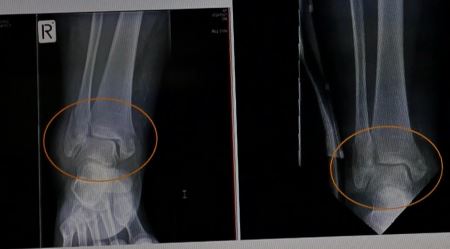

救护人员快速的把我抬到救护车上拉到急救中心,拍了很多X光照片。医生在X光片子上看到右腿有五处粉碎性骨折:右侧的踝骨和膝盖链接的腓骨完全断了,穿着裤子就可以明显看到骨折处的骨头向外支出;膝盖骨、右腿的左踝骨、右踝骨、右脚后跟,全部是粉碎性骨折。因为右腿肿的厉害,裤子已经绷的很紧,根本脱不下来,医生就用剪刀把裤子一块一块的剪掉。当时右腿一动也不能动。

'图2:王久春女士2015年11月7日的踝关节X光片(左)与同年12月4日的X光片(右),对比可以看出,车祸3周后骨折处已有愈合趋势。'

图2:王久春女士2015年11月7日的踝关节X光片(左)与同年12月4日的X光片(右),对比可以看出,车祸3周后骨折处已有愈合趋势。

十二月二十三日的复查显示:与十一月七日拍的片子相比较,能看到膝关节有明显的伤后愈合迹象;断骨端对位线良好;甚至那些骨头的碎片好像都是活的一样也在向自己原来的位置移动。